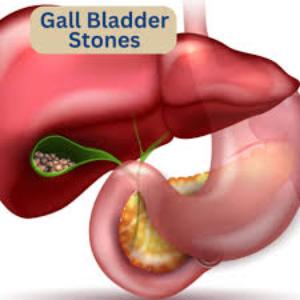

Surgeries We Offer

Gall Bladder Stones